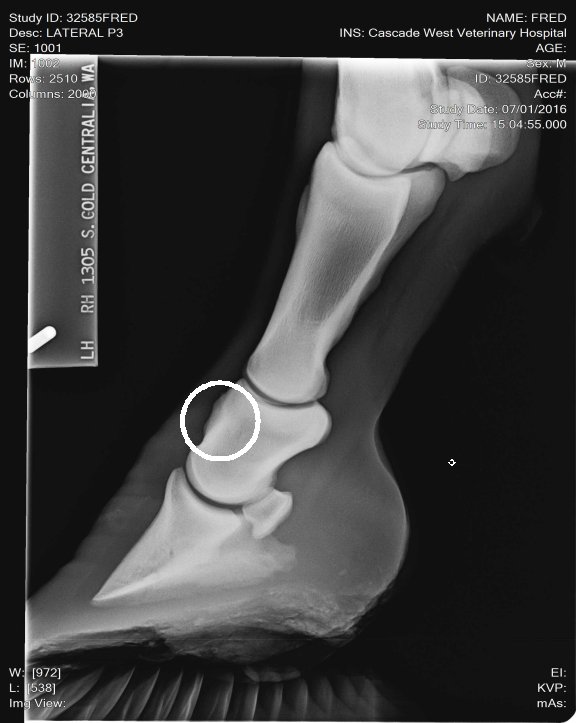

Location: Washington | So we got a young, 3 yr old, horse from some friend to break, put some time on and sale for them. AWESOME little horse with a nice cowbred pedigree. Our 7 yr old was riding him his 14th ride, he now has about 45 days on him. She's now taken over the reins working cows and trail riding. He's had a pretty easy life, no injuries or illness. We started advertising and have LOTS of interest BUT he has failed two pre purchase exams for lameness on the flex test. First was front left yesterday was front right. First vet check took X rays, he said he was clean, vet that looked at him yesterday said no, high ringbone! He rides sound but wont pass the flex tests. What are your expereinces with this? What are our options? Maintence?Β Β We WILL be up front and honest with his condition to potenial buyers but I'd like to know other peoples opinions and your most successful treatments.

I'll try this again I circled the wrong place! lol Thats what I get for doing this before coffee!

Location: Lost in the swamps | My opinion these X rays don't look bad. I don't see any involvement in the joint spaces. I've seen a lot worse. He's got really long toes, you need to show your farrier these x rays and have him shorten and round his toes to quicken his break over is very important for horses dealing with ringbone. long toes create a lot of torque! This can also lead to lamine inflammation. The p-1 and p-2 is a low motion joint so it can actually fuse and the horse still have soundness. Your p2 and coffin joint is where you don't want any issues of ring bone. And I don't see any there. The upper pattern has some oddity near the seasmoid bone. Just curious did your vet mention anything? |